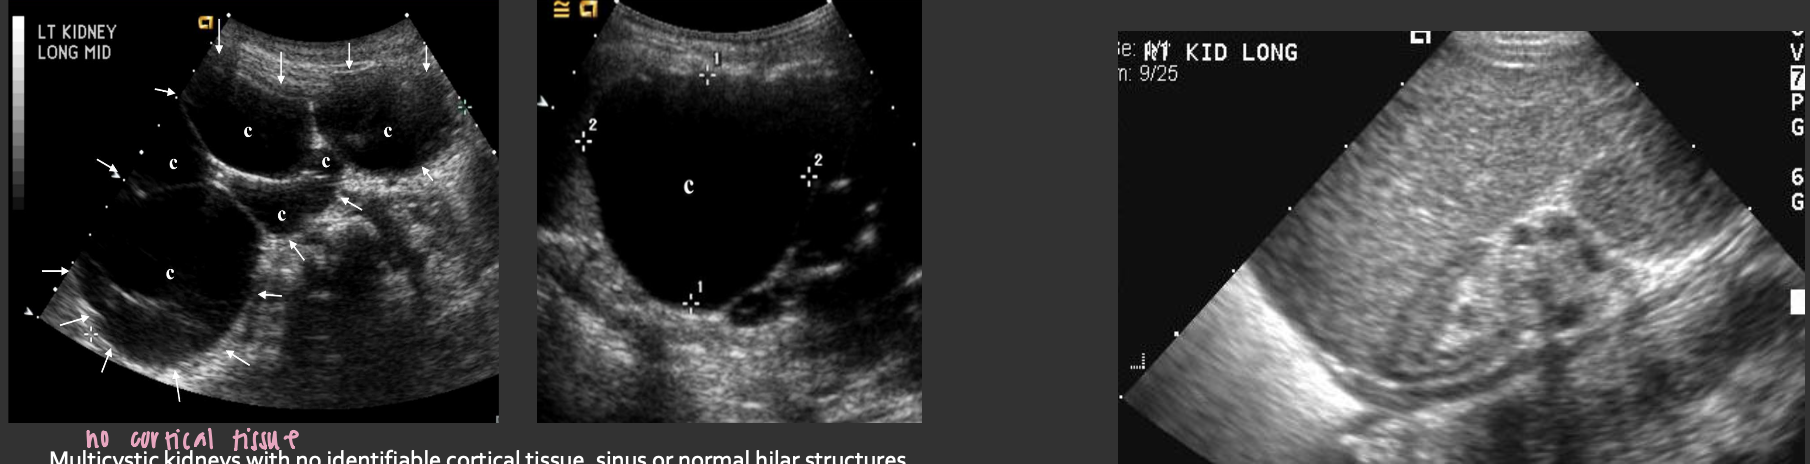

MCDK (Multicystic Dysplastic Kidney) → common acquired renal dysplasia

clinical hx: male

s/sx: asymptomatic

2D US: unilateral (bilateral incompatible with life), multiple non communicating cysts, absence of normal cortex and sinus, initially → enlarged kidney, in adults → atrophic kidney that may become calcified

color doppler: avascular

DDX: ADPKD